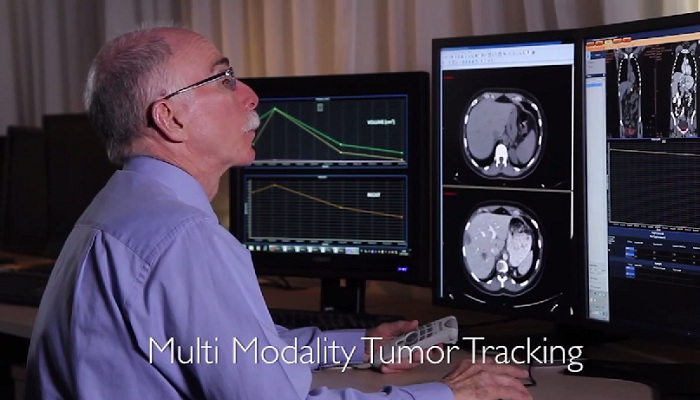

Having diagnostic confidence has always been your goal. With today’s value-based reimbursement structures and demand for improved clinical outcomes, it’s increasingly becoming a necessity. Each step of the diagnostic process should be both and provide quality actionable results. To help this, we provide: Learn how our radiology solutions can help you reach clinical diagnoses efficiently and with confidence.

“By using Philips’ advanced imaging techniques like 3D, MIP, and MPR, we can easily bring up images and manipulate them to fine-tune our diagnoses. We get a better idea of the extent of the disease and can make better recommendations to the clinician about what’s going on.” Dr. D’Arcy Little

MD, CCFP, FRCP, Radiologist, Orillia Soldiers’ Memorial Hospital, Orillia, Ontario